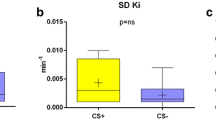

Moreover, SUV and MRglc for sarcoid lesions were significantly lower than those for malignant lesions (SUV, 4.98 ± 2.00 vs 6.21 ± 2.14; MRglc, 2.52 ± 1.39 vs 3.68 ± 1.61; p < 0.01). ROC analysis revealed that the ability to discriminate sarcoid lesions from malignant lesions yielded an AUC of 0.694, with 54% sensitivity, and 75% specificity for SUV of 4.715, and an AUC of 0.735, with 61% sensitivity, and 81% specificity for MRglc of 2.475 (Fig. 3).

a (Left) Box-and-whisker plots of SUV for sarcoidosis lesions and malignant lesions. SUV for sarcoid lesions was significantly lower than those for malignant lesions (4.98 ± 2.00 vs 6.21 ± 2.14; *p < 0.01). (Right) Box-and-whisker plots of MRglc for sarcoidosis lesions and malignant lesions. MRglc for sarcoid lesions were significantly lower than those for malignant lesions (2.52 ± 1.39 vs 3.68 ± 1.61; *p < 0.01). b (Left) The diagnostic performance of sarcoidosis lesions using SUV. ROC analysis revealed that the ability to discriminate sarcoid and malignant lesions yielded an AUC of 0.694, with 54% sensitivity and 75% specificity for SUV 4.715. (Right) The diagnostic performance of sarcoidosis lesions using MRglc. ROC analysis revealed that the ability to discriminate sarcoid and malignant lesions yielded an AUC of 0.735, with 61% sensitivity and 81% specificity for MRglc 2.475. AUC, the area under the curve; MRglc, glucose metabolic rate; ROC, receiver operating characteristic; SUV, standardized uptake value

Lesions with the highest SUV among multiple lesions per patient were considered representative. Furthermore, SUV and MRglc for patients with sarcoid lesions were significantly lower than those for patients with malignant lesions (SUV, 5.07 ± 2.14 vs 6.47 ± 2.31; MRglc, 2.55 ± 1.52 vs 3.84 ± 1.70; p < 0.01). The optimal cutoff values of SUV and MRglc were 5.025 and 2.855, respectively. The values that distinguished patients with sarcoid lesions from those with malignant lesions had AUC of 0.703 and 0.754, sensitivities of 64% and 77%, and specificities of 75% and 72%, respectively (Fig. 4). The average number of multiple lesions per patient was used as the representative value. SUV and MRglc for patients with sarcoid lesions were significantly lower than those for patients with malignant lesions (SUV, 4.77 ± 1.91 vs 6.04 ± 1.92; MRglc, 2.42 ± 1.36 vs 3.55 ± 1.42; p < 0.01 for all). The optimal cut-off values of SUV and MRglc were 4.858 and 2.475, respectively. The values distinguishing patients with sarcoid lesions from those with malignant lesions had AUC of 0.717 and 0.746, sensitivities of 66% and 66%, and specificities of 72% and 79%, respectively. Two representative cases of sarcoidosis and malignant lesions are shown in Figs. 5 and 6, respectively.

a (Left) Box-and-whisker plots of SUV for patients with sarcoidosis lesions and malignant lesions. SUV for patients with sarcoid lesions was significantly lower than that for malignant lesions (5.07 ± 2.14 vs 6.47 ± 2.31; *p < 0.01). (Right) Box-and-whisker plots of MRglc for patients with sarcoidosis lesions and malignant lesions. MRglc for patients with sarcoid lesions was significantly lower than that for malignant lesions (2.55 ± 1.52 vs 3.84 ± 1.70; *p < 0.01). b (Left) The diagnostic performance of patients with sarcoidosis lesions using SUV. ROC analysis revealed that the ability to discriminate patients with sarcoid and malignant lesions yielded an AUC of 0.703, with 64% sensitivity and 75% specificity for SUV 5.025. (Right) The diagnostic performance of patients with sarcoidosis lesions using MRglc. ROC analysis revealed that the ability to discriminate sarcoid and malignant lesions yielded an AUC of 0.754, with 77% sensitivity and 72% specificity for MRglc 2.855. AUC, the area under the curve; MRglc, glucose metabolic rate; ROC, receiver operating characteristic; SUV, standardized uptake value